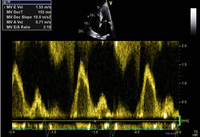

Fluxo de entrada mitral confirmando enchimento restritivo

Do acervo de Dr Jessica Webb; usado com permissão